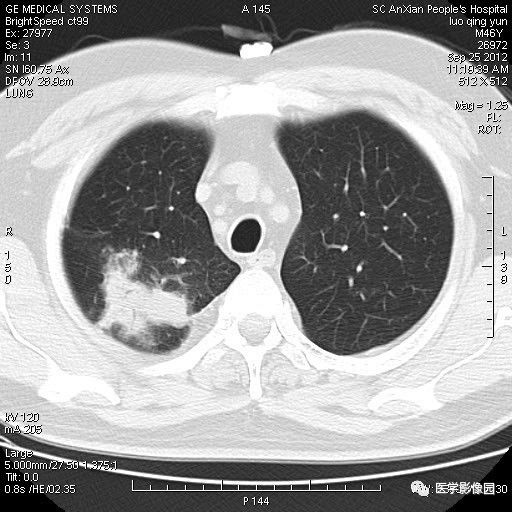

影像学表现:右上肺见不规则团块状高密度阴影,略有分叶级毛刺,边缘模糊,邻近胸膜增厚,增强扫描呈轻中度强化。

诊断结果:右上肺炎性假瘤

本病影像学表现无绝对特征性。单发多见,多位于肺表浅部位,多呈圆形或椭圆形,直径多在2-5cm或更大;多有假包膜,边缘多清晰光整,有时也毛糙,并可有分叶或毛刺;邻近胸膜局限性增厚、牵拉,病灶边缘呈桃尖样突起即桃尖征(尖端指向胸膜);增强扫描多呈中度均匀强化,持续时间较长。亦可显著强化。